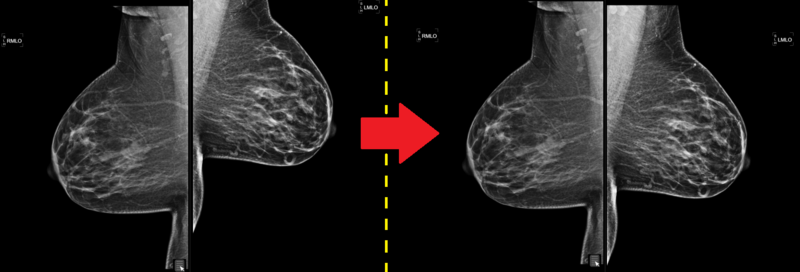

The images will re-align accordingly, an examples is shown below: